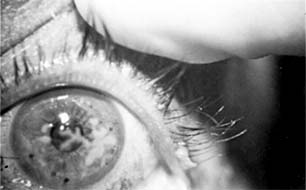

Pseudomonas corneal ulcer begins as a gray or yellow infiltrate at the site of a break in the corneal epithelium (Figure 6-2). Severe pain usually accompanies it. The lesion tends to spread rapidly in all directions because of the proteolytic enzymes produced by the organisms. Although superficial at first, the ulcer may affect the entire cornea. There is often a large hypopyon that tends to increase in size as the ulcer progresses. The infiltrate and exudate may have a bluish-green color. This is due to a pigment produced by the organism and is pathognomonic of P aeruginosa infection.

Figure 6-2

Figure 6-2: Pseudomonsa ulcer related to 24-hour contact lens wear.

Pseudomonas is a common cause of bacterial corneal ulcers. Cases of Pseudomonas corneal ulcer may follow minor corneal abrasion or the use of soft contact lenses-especially extended wear lenses. Corneal ulcers caused by this organism can vary from quite benign to devastating. The organism has been shown to adhere to the surface of soft contact lenses. Some cases have been reported following the use of contaminated fluorescein solution or eye drops. It is mandatory that the clinician use sterile medications and sterile technique when caring for patients with corneal injuries.